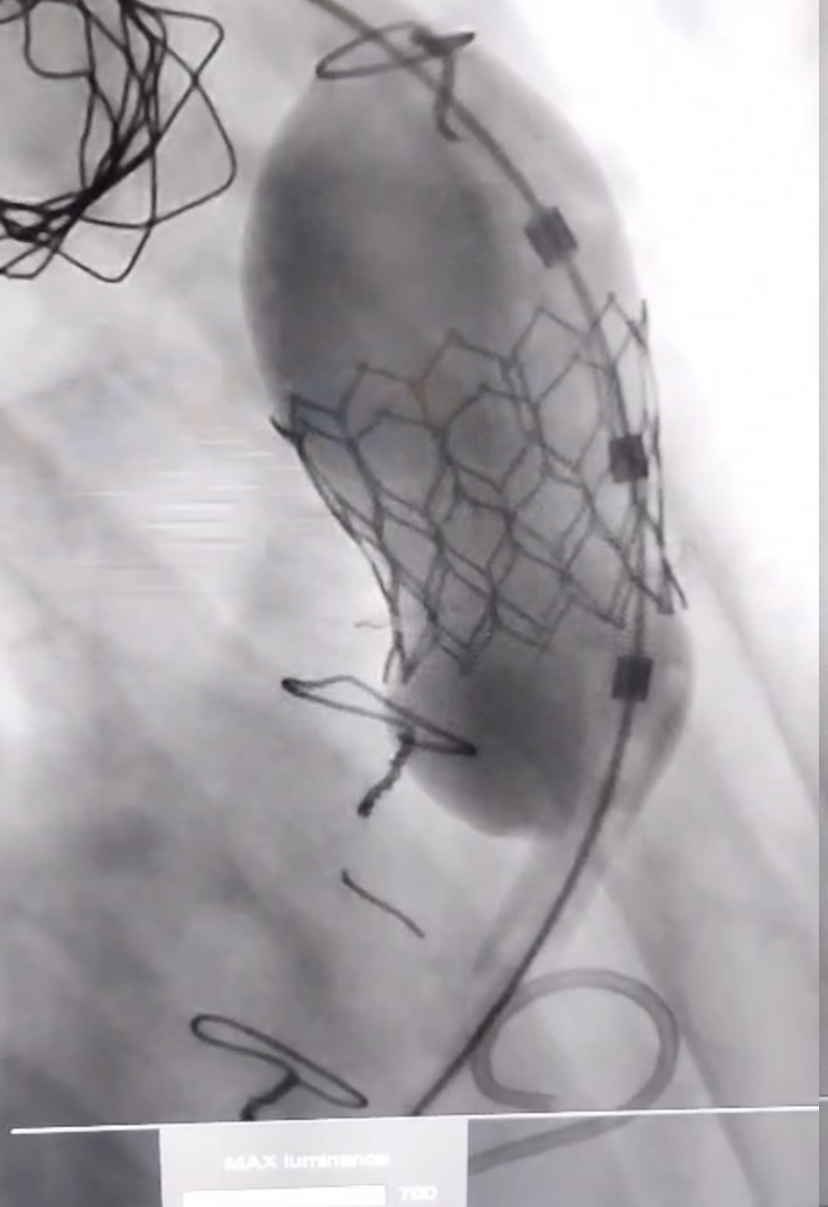

Se realizó con éxito en IDYTAC el primer procedimiento valve-in-valve percutáneo en un paciente con Tetralogía de Fallot en La Plata, y posiblemente el primero en la provincia de Buenos Aires, utilizando la válvula Myval 24,5 mm.

Visualización completa del procedimiento valve-in-valve con válvula Myval

La intervención se realizó mediante técnica de valve-in-valve, previa fractura con balones de 20 y 22 mm, y posterior colocación de válvula Myval 24,5 mm, con resultado altamente favorable.